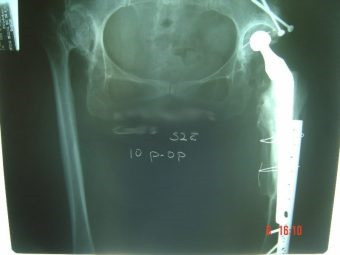

Revisión de prótesis con injerto óseo masivo

Envíado por Dr. Ricardo Antonio Gómez G.